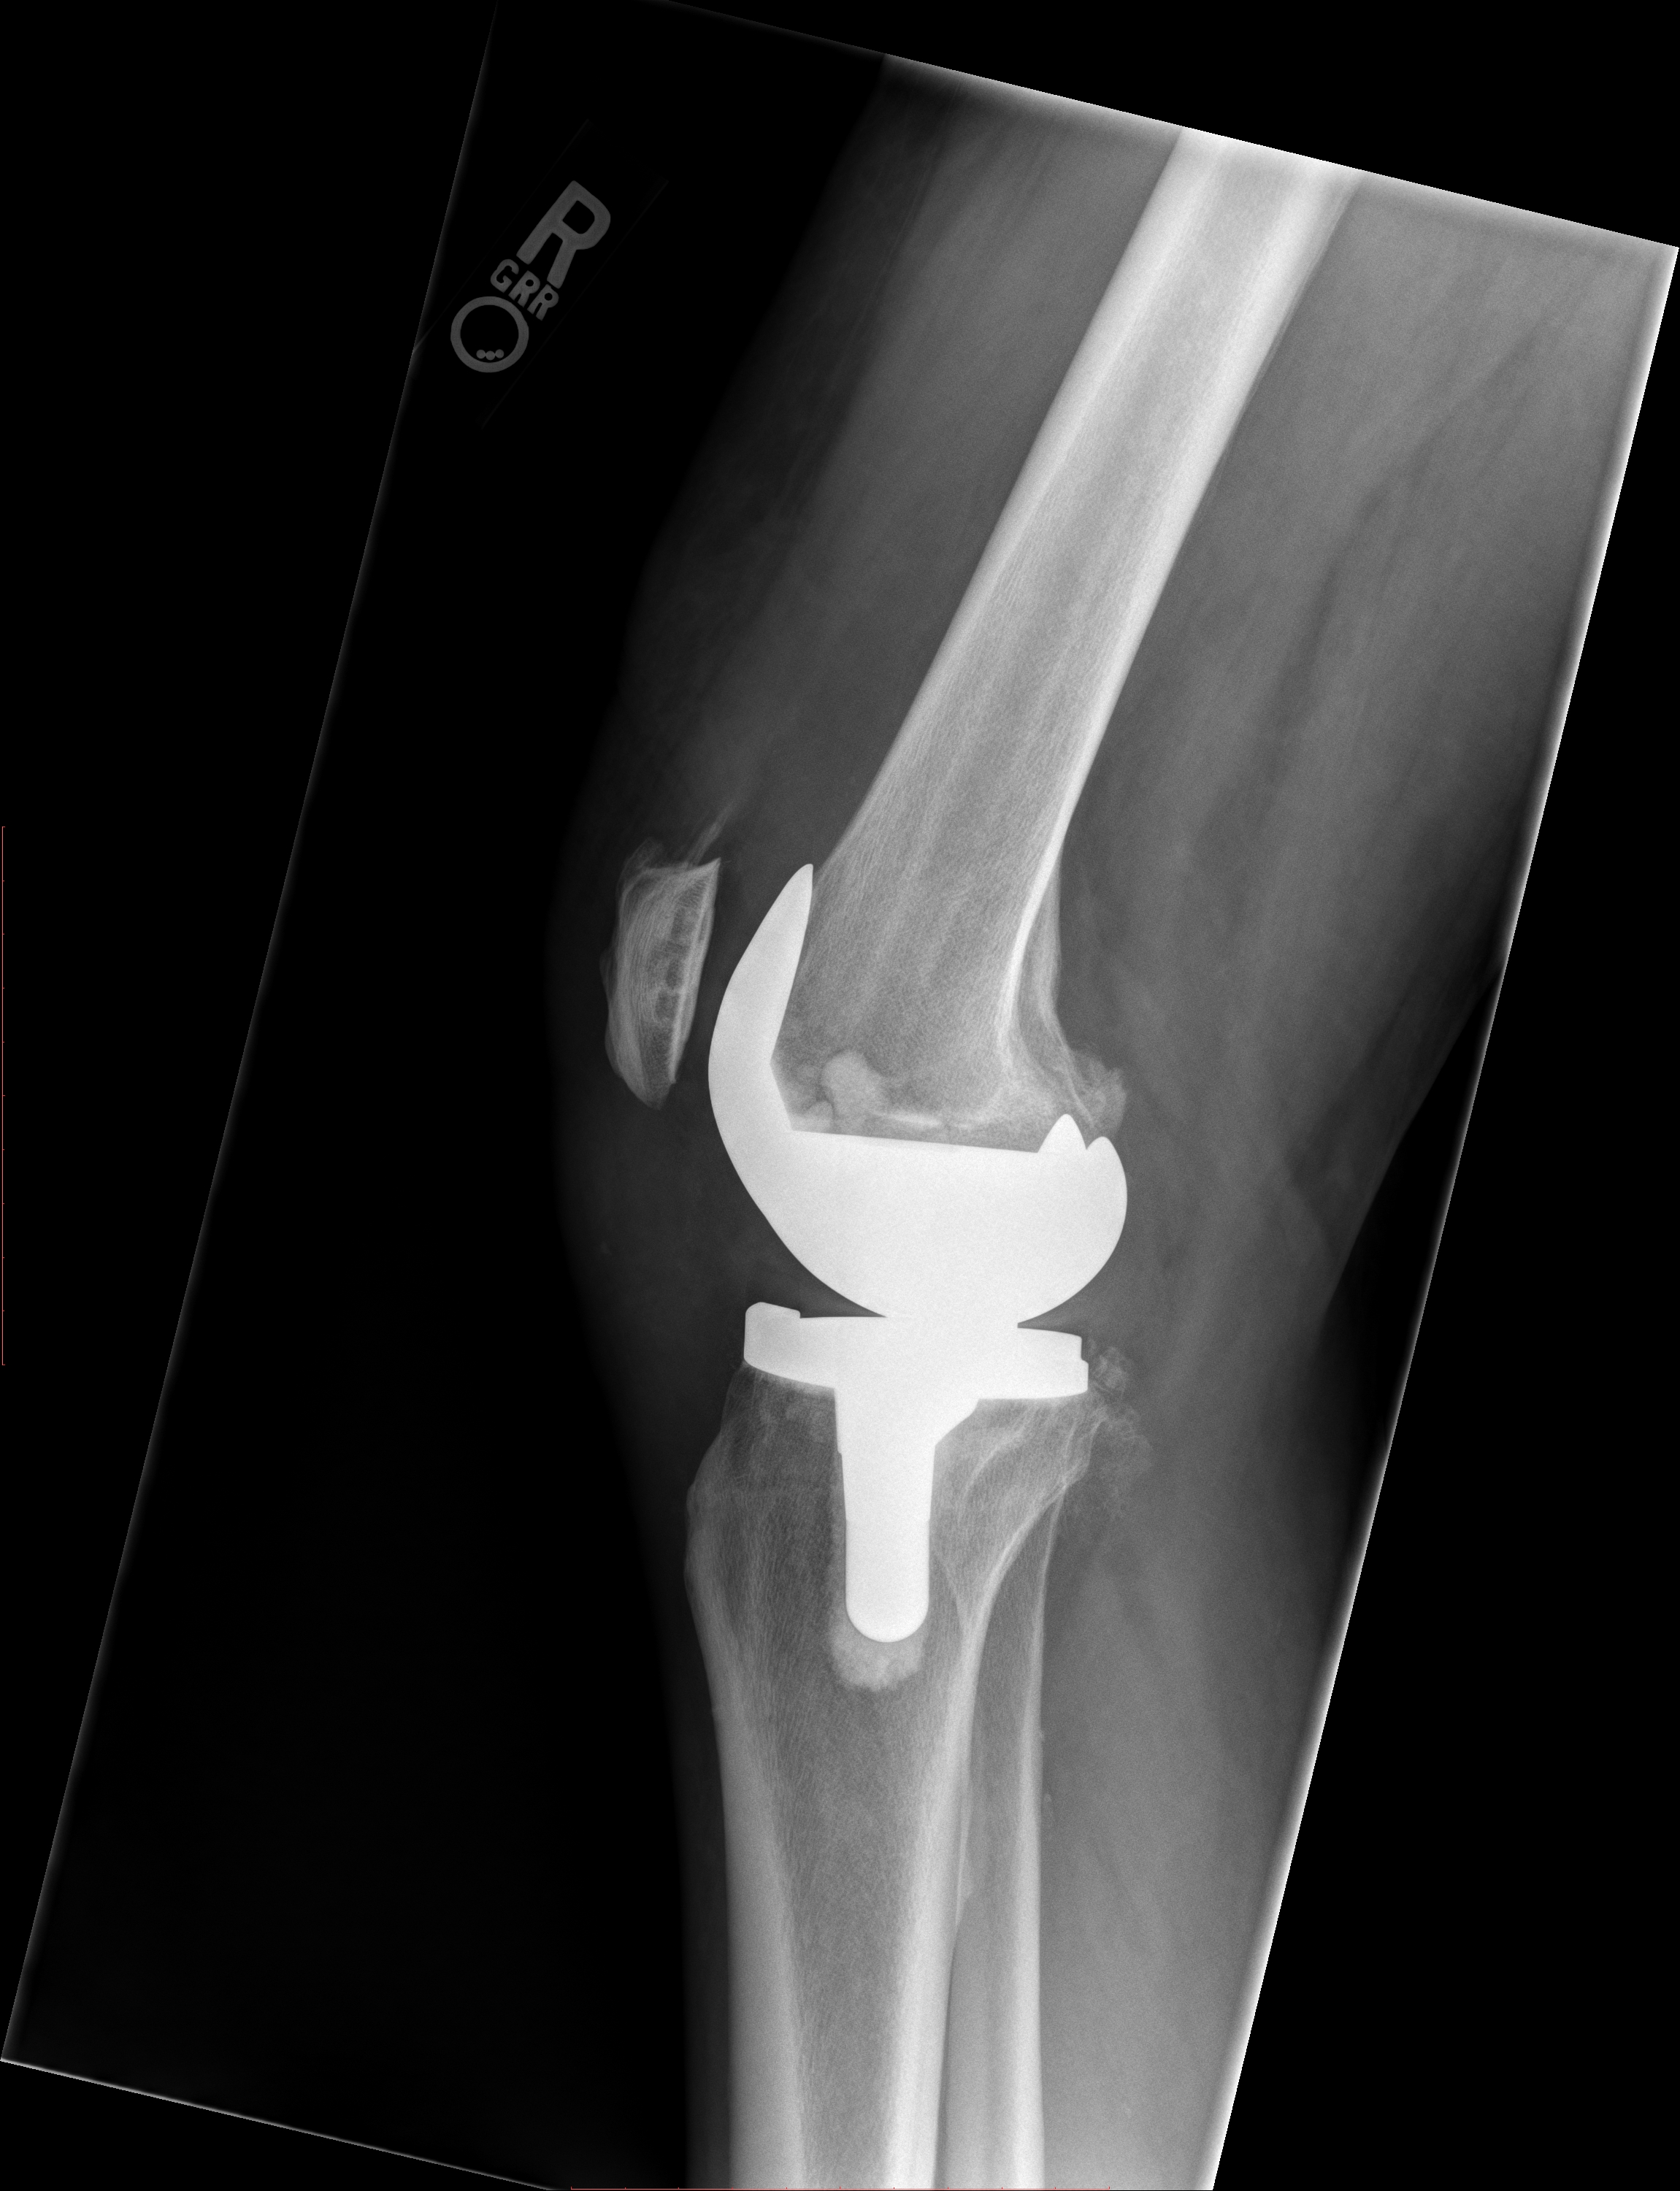

X-rays following 26AUG19 surgery, 26AUG19 (click to enlarge):

X-ray by Sutter Davis Hospital